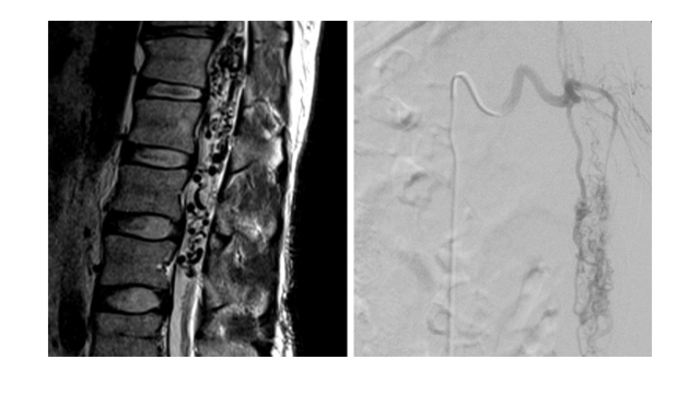

5:磁共振矢状位(左)和脊髓血管造影前后位(右)显示髓周动静脉瘘。注意到马尾区域粗大迂曲扩张的髓周血管流空影。患者行导管内栓塞治疗。由于涉及马尾区域,如采用开放手术很难全切病变。